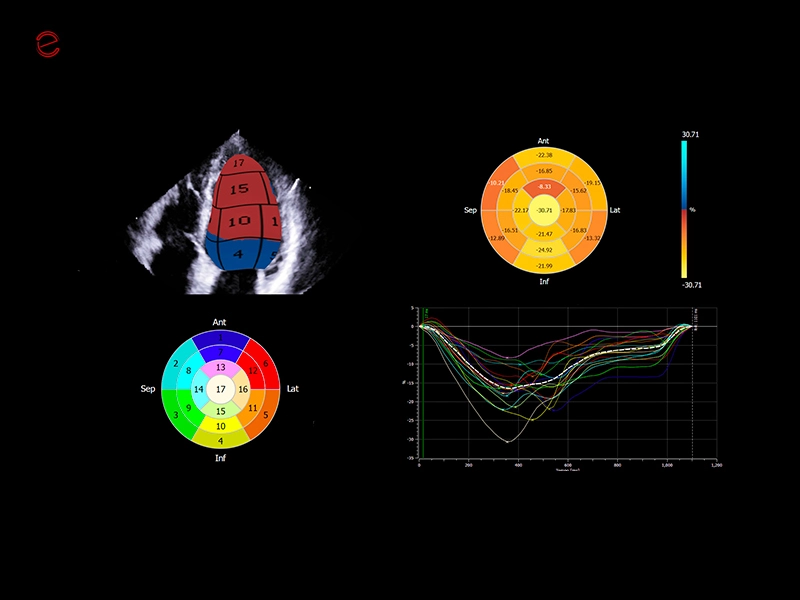

MyLab™X90 - XStrain™ LV Automatic assessment of global longitudinal strain in the left ventricle

MyLab™X90 - XStrain™ LV Automatic assessment of global longitudinal strain in the left ventricle